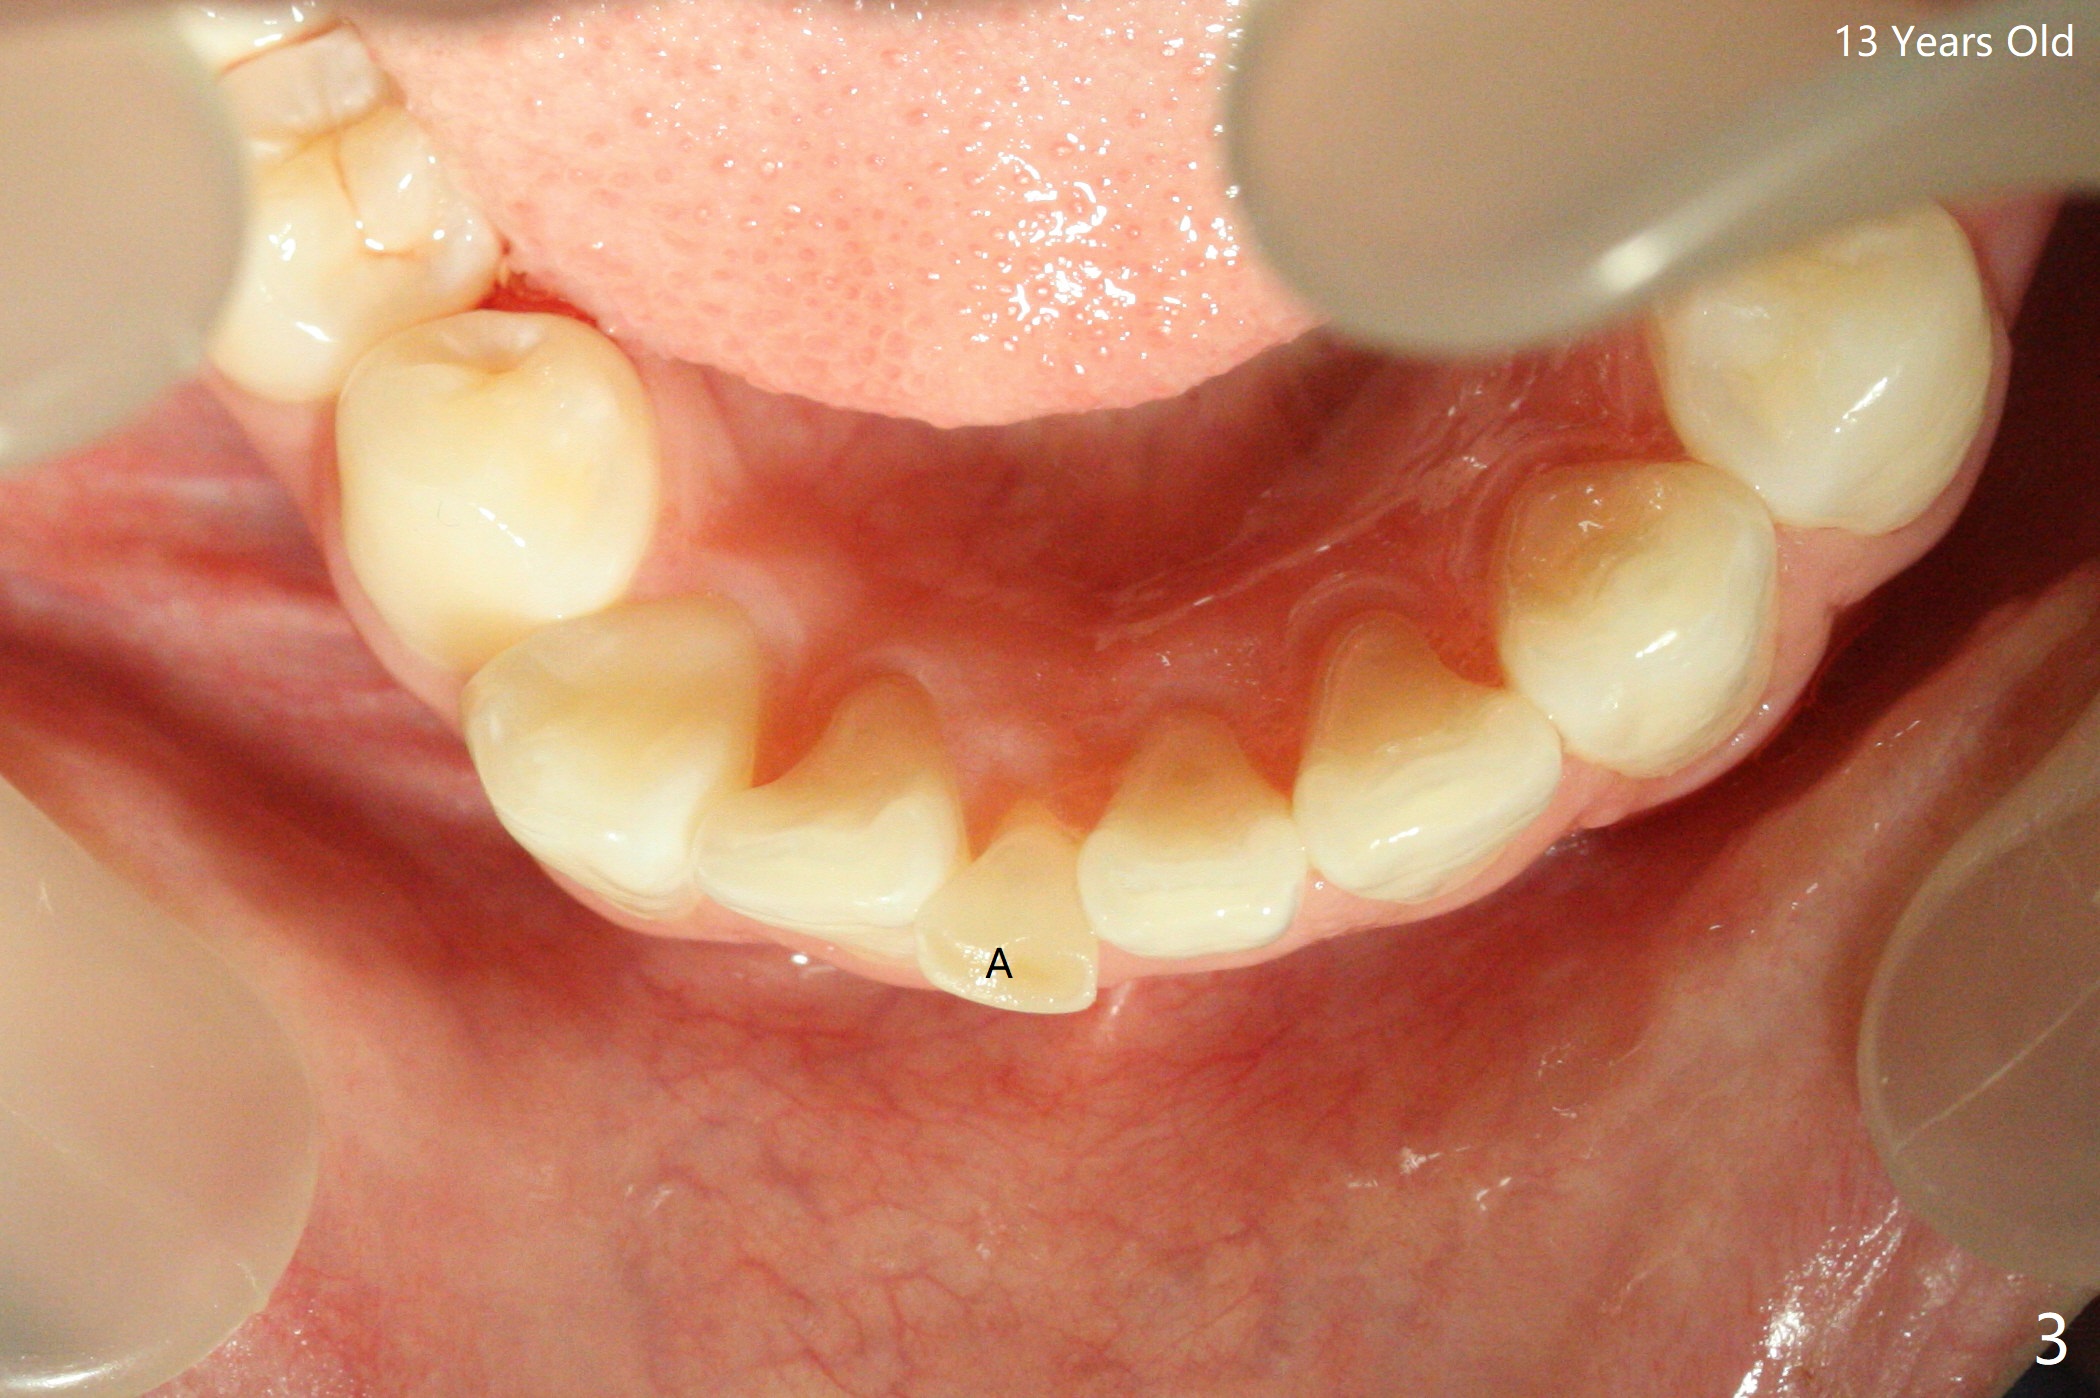

A 7-year-old woman has congenital missing lower right central incisor (Fig.1). At age of 13, she requests extraction of the displaced and discolored deciduous central incisor (Fig.2,3 A). After extraction, self drifting may alleviate crowding and anterior overjet and closes the space? Perfect solution, extract the A followed by driftodontics...fixed appliances as needed. Dr. Shaughness 12/25/2019